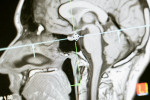

Μια νέα μελέτη σε ποντίκια δίνει πλέον μια πιθανή μοριακή απάντηση σε αυτό το ιατρικό αίνιγμα. Μια πρωτεΐνη που παράγεται από καρκινικά κύτταρα φαίνεται να περνά στον εγκέφαλο, όπου συμβάλλει στη διάσπαση συσσωματωμάτων λανθασμένα αναδιπλωμένων πρωτεϊνών, τα οποία συνδέονται στενά με τη νόσο Αλτσχάιμερ. Η μελέτη, η οποία χρειάστηκε 15 χρόνια για να ολοκληρωθεί, δημοσιεύτηκε στις 22 Ιανουαρίου στο επιστημονικό περιοδικό Cell και θα μπορούσε να ανοίξει τον δρόμο για τον σχεδιασμό νέων θεραπειών κατά της νόσου Αλτσχάιμερ.

Περαιτέρω πειράματα σε ποντίκια έδειξαν ότι η κυστεατίνη C συνδέεται με τα μόρια που σχηματίζουν τις χαρακτηριστικές πλάκες της νόσου Αλτσχάιμερ. Αυτή η αλληλεπίδραση ενεργοποιεί μια πρωτεΐνη σηματοδότησης, την TREM2, η οποία βρίσκεται σε ορισμένα ανοσοκύτταρα που επιτηρούν τον εγκέφαλο.

Στη συνέχεια, τα ανοσοκύτταρα αυτά διασπούν τις πλάκες. Στα ποντίκια του Lu, η διάσπαση των πλακών συνδέθηκε με καλύτερη απόδοση σε γνωστικά τεστ.